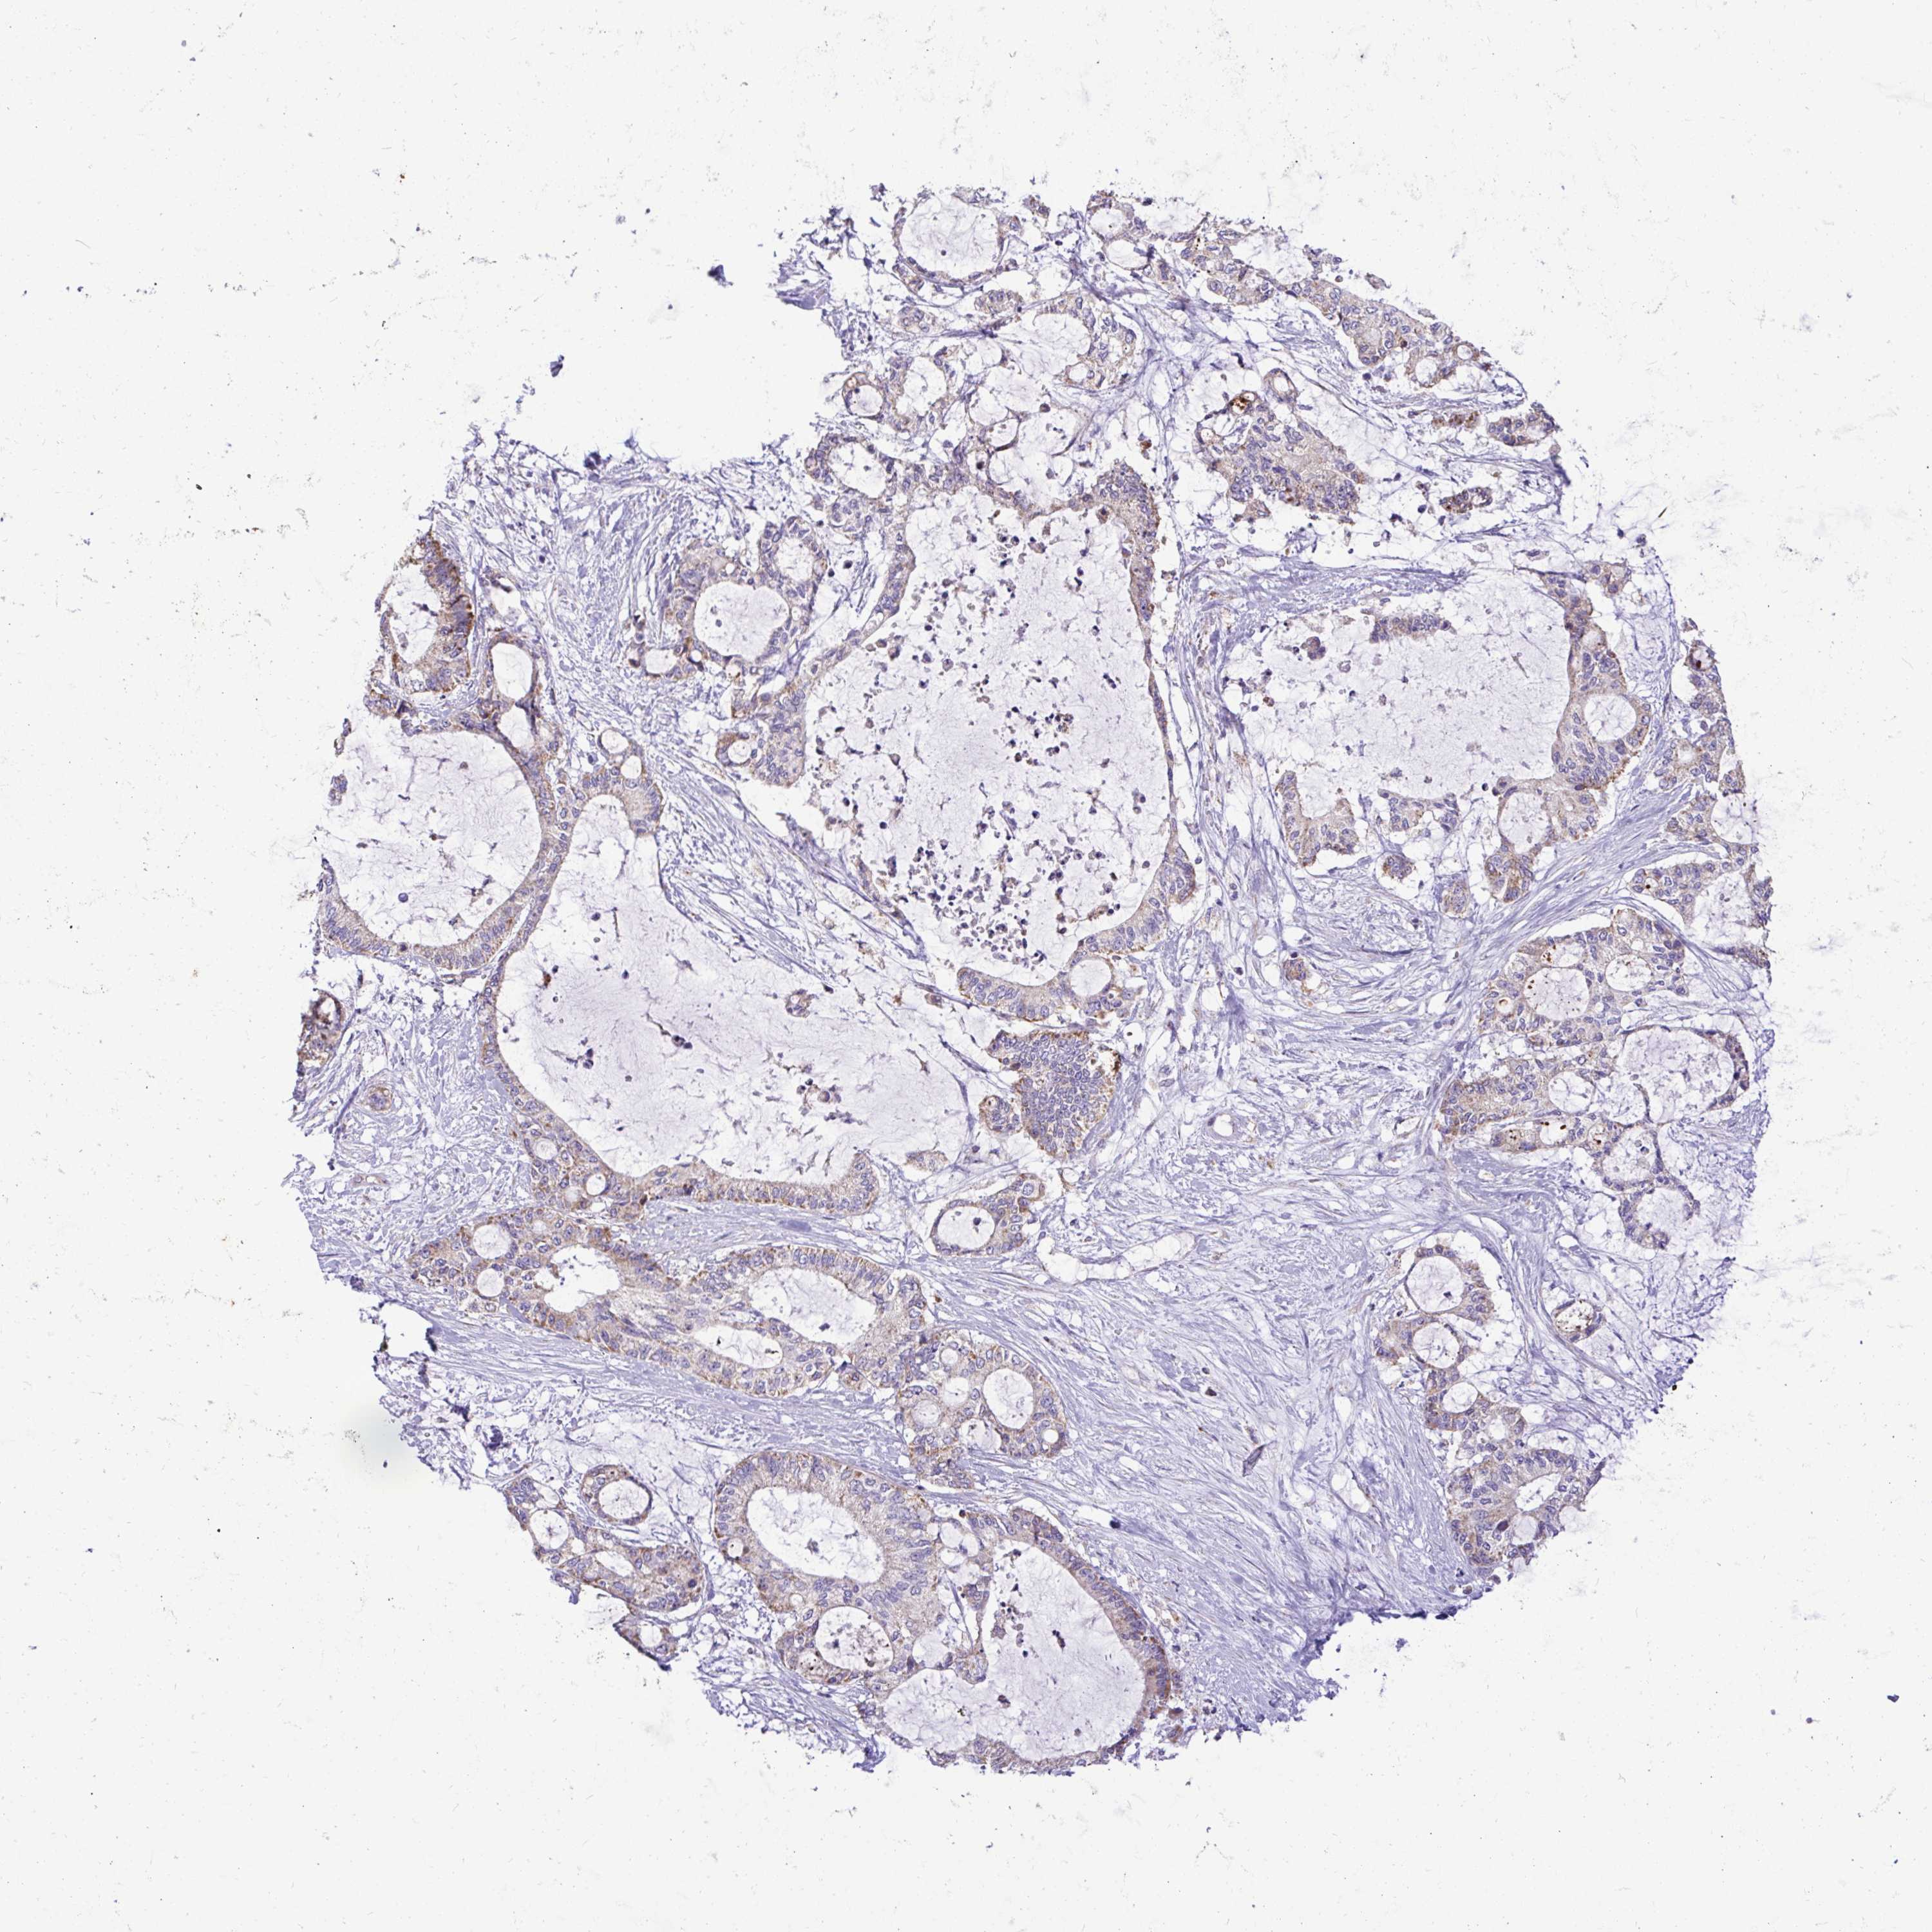

LIVER CANCER - Protein expressioni

A mouse-over function shows sample information and annotation data. Click on an image to view it in a full screen mode. Samples can be filtered based on level of antibody staining by selecting one or several of the following categories: high, medium, low and not detected. The assay and annotation is described here.

Note that samples used for immunohistochemistry by the Human Protein Atlas do not correspond to samples in the TCGA dataset.

Antibody stainingi

Antibody staining in the annotated cell types in the current human tissue is reported as not detected, low, medium, or high, based on conventional immunohistochemistry profiling in selected tissues. This score is based on the combination of the staining intensity and fraction of stained cells.

Each image is clickable and will lead to virtual microscopy that enables deeper exploration of all samples and also displays staining intensity scores, fraction scores and subcellular localization as well as patient and tissue information for each sample.

Antibody HPA057267

Antibody HPA058086

Staining

High

Medium

Low

Not detected

Intensity

Strong

Moderate

Weak

Negative

Quantity

>75%

75%-25%

<25%

None

Location

Nuclear

Cytoplasmic/membranous

Cytoplasmic/membranous,nuclear

Carcinoma, Hepatocellular, NOS

Cholangiocarcinoma